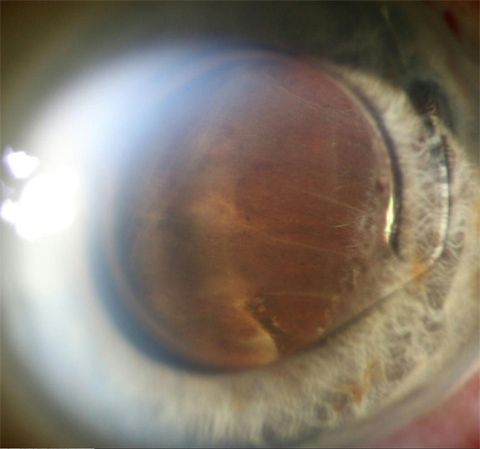

Anterior suprachoroidal hemorrhage abutting anterior chamber intraocular lens

Spontaneously dislocated lens with ring-shaped pigmentation